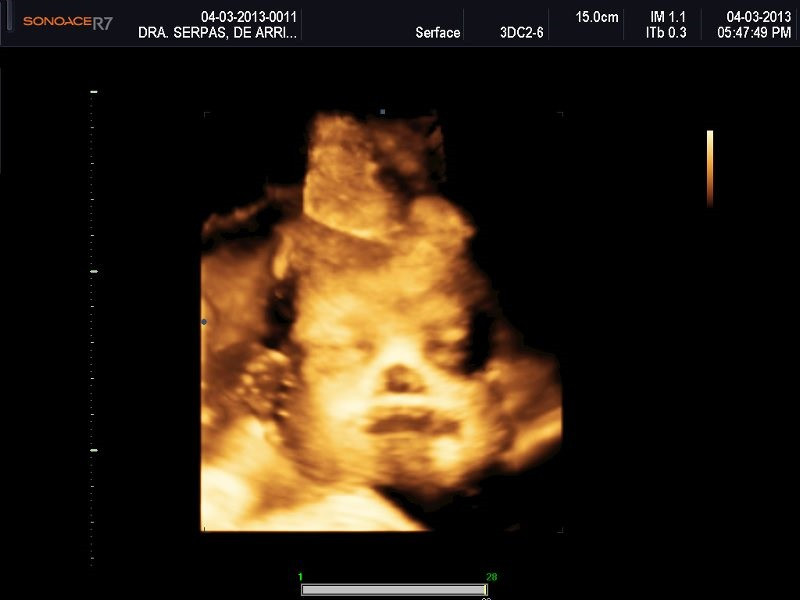

Varias ultrasonografías en 2D y 3D

Envíado por Dr. Nelson Menjívar Sarco